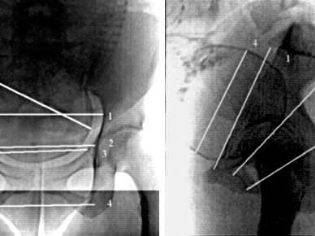

Рентгенопельвиометрия – способ оценки размеров таза, проводимый после 37 недели беременности. С помощью рентгенограммы можно выяснить строение стенок таза, а также особенности лонной дуги, кривизну крестца и положение седалищных костей. Рентген выявляет положение головки плода относительно плоскости таза. Также можно выяснить, есть ли у девушки переломы или опухоли в области этого пояса.

Что касается прогноза родов на основании рентгенологических данных при беременности, то следует отметить, что существующие методы рентгенографии таза роженицы и головки плода не дают возможности установить точные соотношения между тазом и головкой и определить ход механизма родов. Только рентгенологические данные для прогноза родов могут иметь значение лишь при резкой степени сужения таза и его деформации. Для установления прогноза родов, кроме размеров таза, играют роль размеры головки плода, характер родовой деятельности, способность головки к конфигурации.

Представляет интерес интерпретация данных рентгеноцефалопельвиметрии для оценки таза и прогноза родов. С этой целью предложено большое число методов.

Соотношение головки плода и таза женщины.

W. Mobius (1957) считал возможным на основании проведенных на рентгенограммах таза измерений истинной конъюгаты и поперечного размера головки плода решать вопрос о соразмерности ее и таза матери. Наиболее благоприятным соотношением он считал преобладание истинной конъюгаты над большим поперечным размером головки на 15 мм для первородящих и на 10 мм у повторнородящих. При меньших соотношениях указанных размеров плода и таза матери детская смертность повышалась на 8,2%.

Нельзя полностью согласиться с мнением упомянутых авторов, которые только на основании индекса емкости таза, вычисленного по произведению или сумме величин прямого и поперечного размеров таза, по планиметрическому измерению площади входа в малый таз определяют прогноз родов. Они не учитывают форму малого таза и другие факторы, имеющие большое значение в процессе и исходе родов. W.F. Mengert (1954), J. Donald (1955) и др., широко используя рентгенопельвиметрию, при решении вопроса о родоразрешеннп совсем отказались от клинических методов измерения таза. Как показывает наш опыт по применению рентгенопельви-метрии для определения размеров таза и соразмерности головки плода и таза матери, на основании данных только рептгенопельвиметрии нельзя окончательно решать вопрос о ведении родов. Мы полностью разделяем мнение тех авторов, ко торые считают, что рентгенопельвиметрия является дополнительным методом уточнения размеров и формы таза и должна проводиться по показаниям.

Существует много методологических проблем, которые заставляют критически относиться к рентгенопельвиметрии как одному из диагностических методов в акушерстве (отсутствие единого подхода к интерпретации данных рентгенопельвиметрии отсутствие четких критериев, обусловливающих необходимость оперативного вмешательства и др.).

Рентгенопельвиометрия проводится по специальным показаниям на сроке не ранее 37 недель беременности. Также данное диагностическое исследование может проводиться в родах.

Рассчитать срок беременности

Рентгенопельвиометрия дает возможность определить морфологию тазовых стенок, форму входа, степень наклона тазовых стенок, особенности строения и расположения относительно друг друга седалищных костей, а также кривизну крестца. Кроме того, подобный метод инструментальной диагностики позволяет рассчитать все тазовые диаметры, выявить наличие новообразований, определить величину головки ребенка и ее пространственное положение.